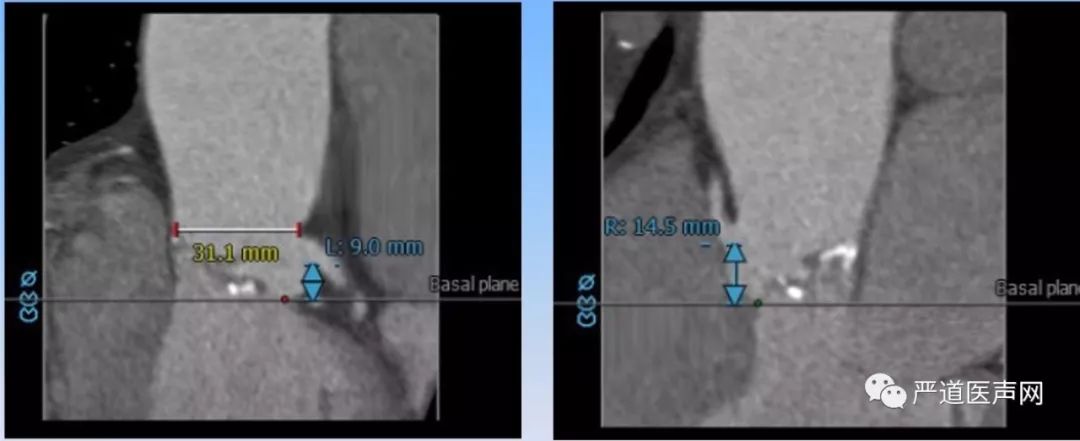

左侧冠脉开口高度较低9.0mm,右侧冠脉开口14.5mm。(如下图)

CTA提示患者瓣膜重度钙化,Type I型二叶主动脉瓣,横位心,主动脉与左心室夹角67°。(如下图)